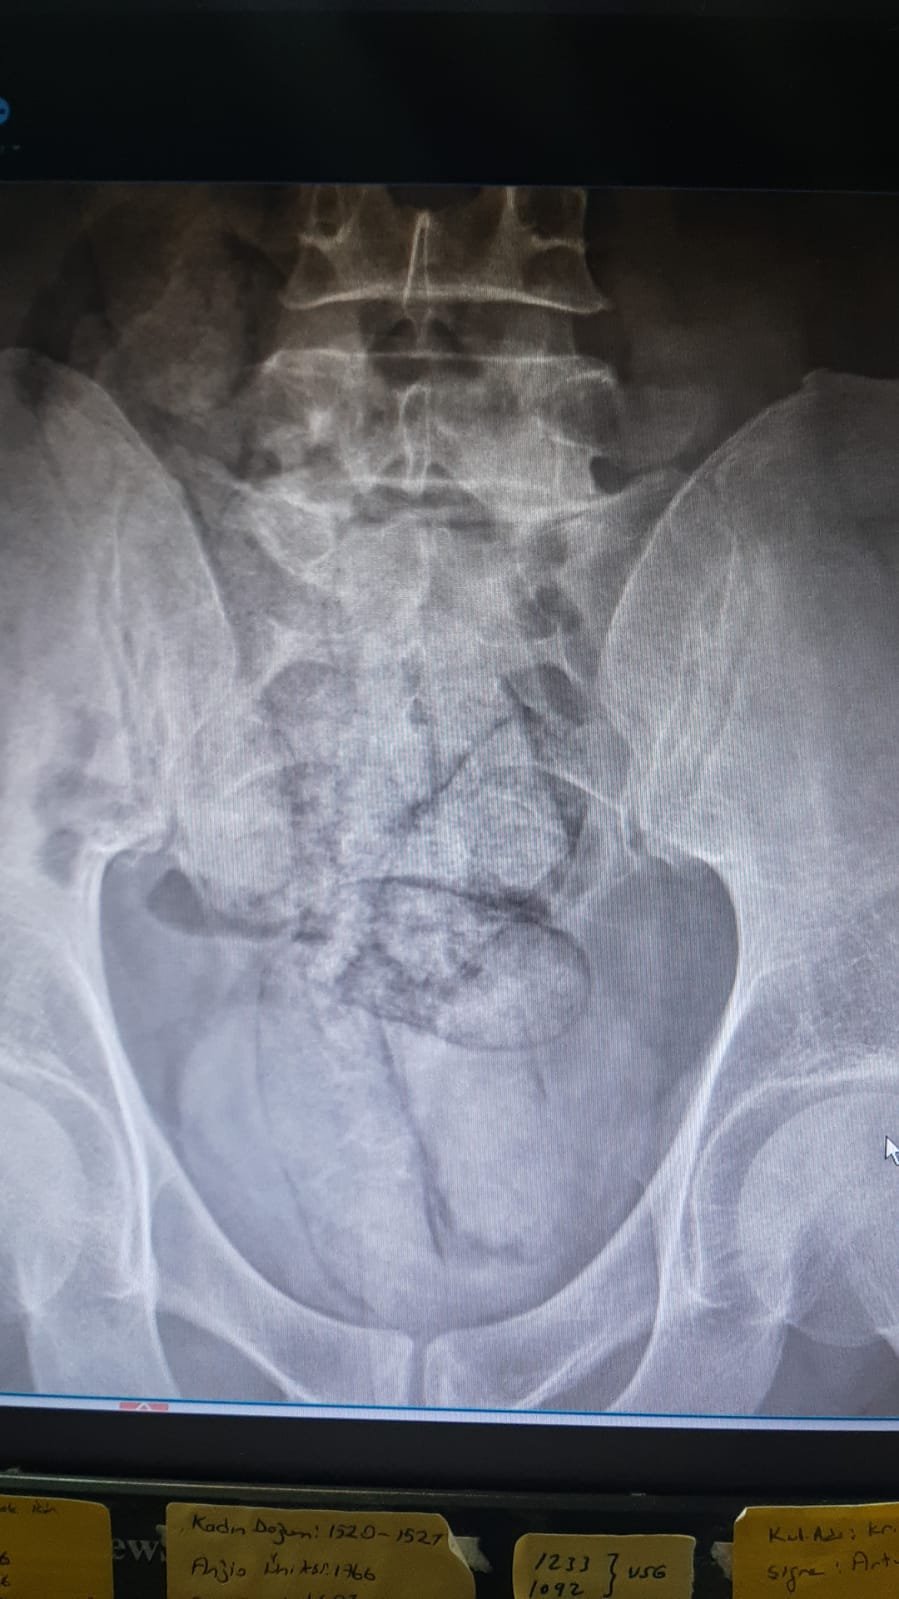

Artvin Devlet Hastanesi'nde tomografisi çekilen şüphelinin bağırsaklarında 10 paket halinde uyuşturucu madde taşıdığı belirlendi. Şüphelinin hayati tehlike oluşturabilecek şekilde sakladığı paketler, cerrahi müdahaleyle çıkarıldı.

İncelemede paketlerin içinde toplam 350 gram metamfetamin olduğu tespit edildi.